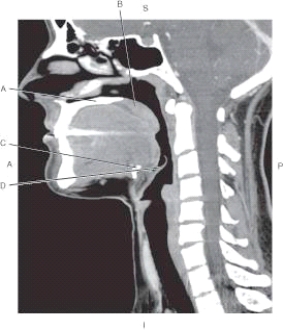

The following questions refer to the figure below of a sagittal CT reformat of the pharynx.

-Which arrow points to the soft palate?